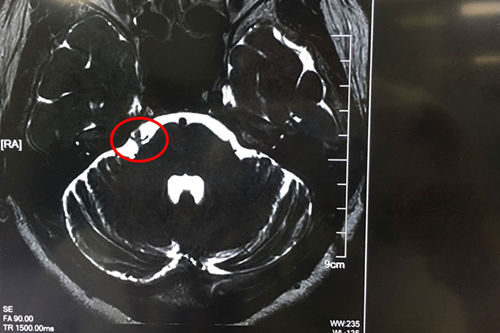

术前核磁影像显示:右侧三叉神经颅内段根部见小血管碰触(两条细小血管跨越并与之接触)